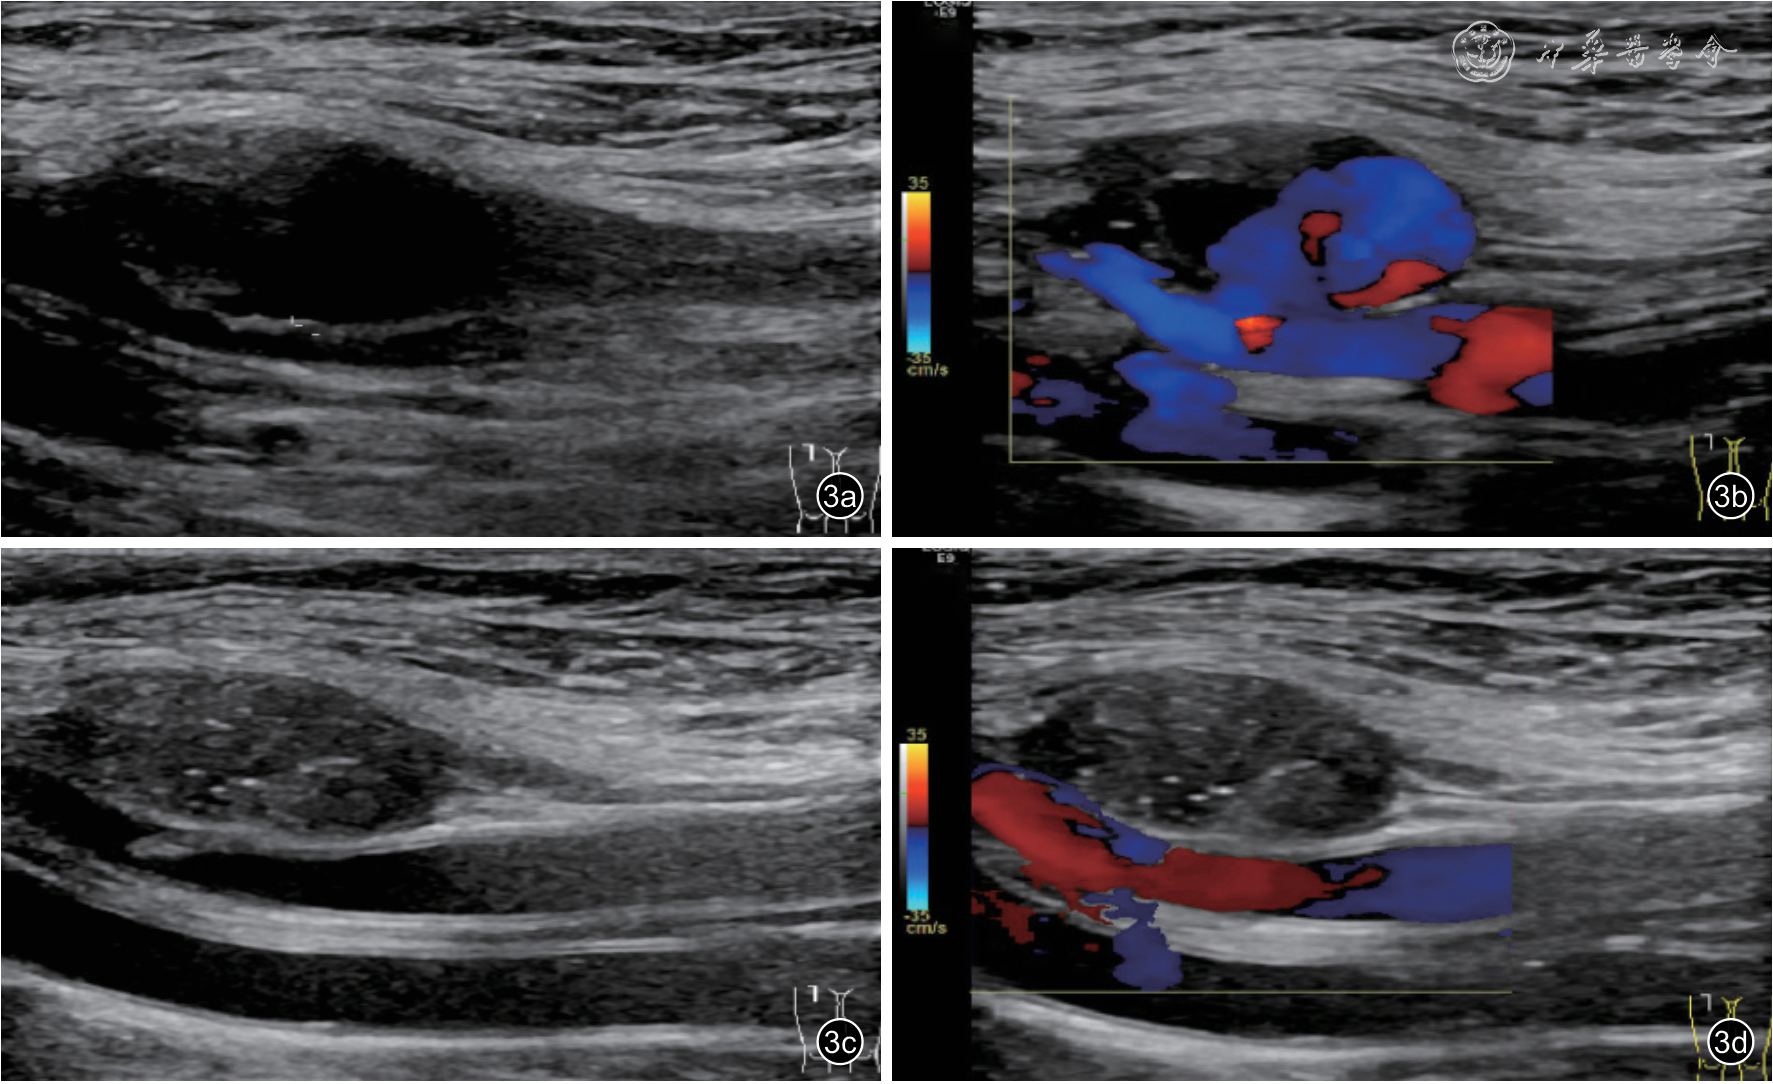

3.UGTI 治疗过程:在常规消毒铺巾后,确认合适的进针路径。使用凝血酶冻干粉溶于生理盐水中形成不同浓度的凝血酶冻干粉生理盐水混悬液。超声引导下采用5 ml 注射器穿刺假性动脉瘤,确认针尖到达瘤体内合适位置后,探头压迫假性动脉瘤,至瘤体体积缩小,瘤体内血流明显减少或无明显血流后,快速注入适量凝血酶冻干粉生理盐水混悬液。在注射过程中,通过二维超声及CDFI 实时动态监测瘤体内血栓形成情况。在瘤内形成血栓的同时,缓慢释放加压探头,直至假性动脉瘤完全回复且瘤内充满血栓,CDFI 确认瘤体内无血流后拔出注射器。术后再次确认瘤体内无血流信号,同时确认足背动脉搏动良好。记录凝血酶使用的剂量及浓度。术后嘱患者卧床休息1 ~2 d,避免患肢过度屈曲压迫瘤体,以免瘤体内的新鲜血栓被挤压出瘤腔进入动脉内,引起远端动脉栓塞。患者术后1、3、6 个月定期行超声随访复查(图3)。

图3 假性动脉瘤超声引导下注射凝血酶治疗术前及术后超声声像图。图a 为术前假性动脉瘤二维超声声像图;图b 为术前假性动脉瘤彩色多普勒血流图;图c 为术后瘤体内血栓形成二维超声声像图;图d 为术后瘤体内血栓形成彩色多普勒血流图